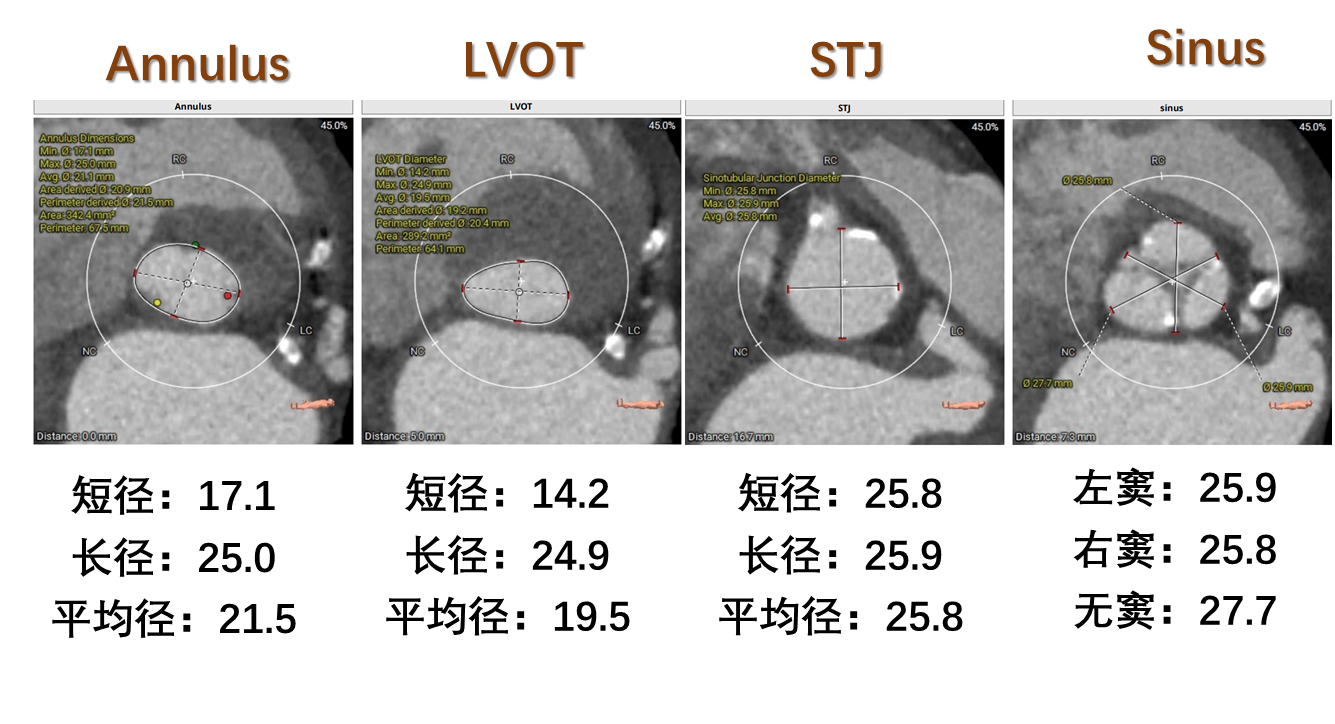

术前CT评估:

瓣膜选择:预装VenusA-Pro 23mm型号瓣膜,18mm球囊预扩,高位释放。